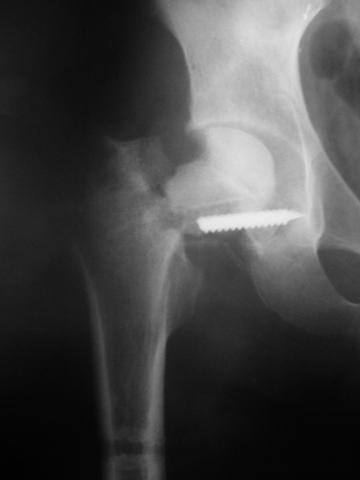

Уважаемые коллеги!молодой человек 22 лет обратился к нам с жалобами на умеренную боль в в/3 левого бедра и паху при ходьбе, укорочение левой ноги. 3 года назад получил закрытый перелом шейки левого бедра (рис 1).